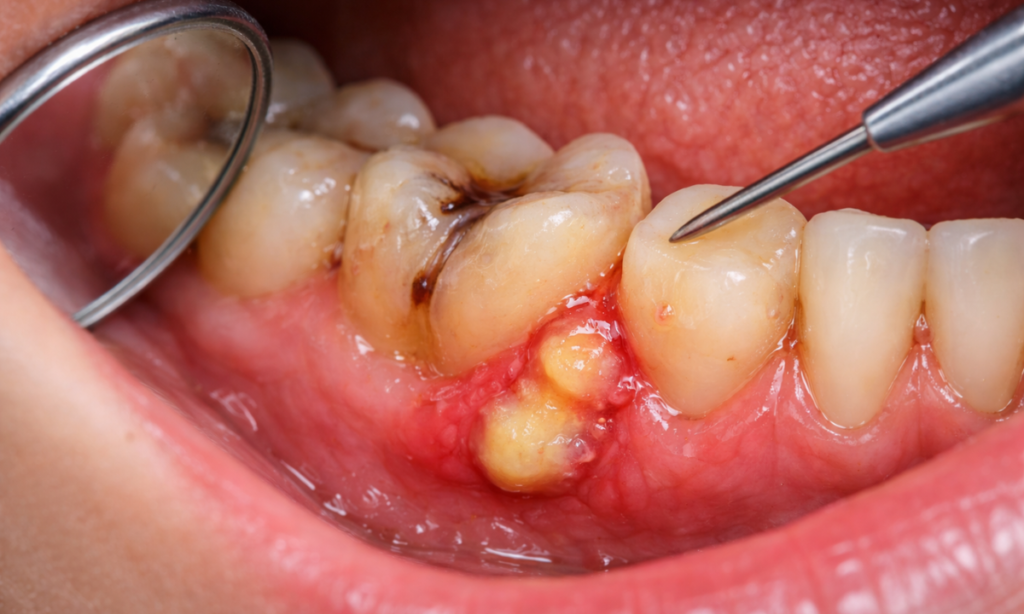

2. Periodontal Abscess (Gum Abscess): This occurs in the gums at the side of a tooth root. It is often caused by severe gum disease or a foreign object, like a popcorn hull getting stuck in the gum pocket.

| Swelling | You may notice a pimple-like bump on your gum. If this ruptures, you might taste a foul-tasting fluid (pus) and feel immediate pain relief, but the infection remains active. |

If you experience these signs, the infection is no longer confined to the tooth. It has likely spread to the jawbone, making radiographic imaging mandatory to assess the damage.